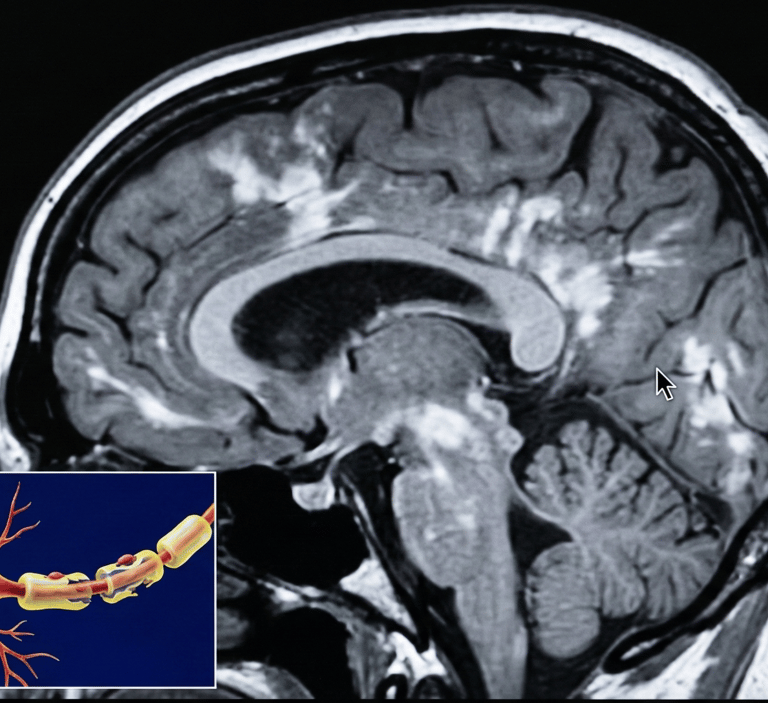

La esclerosis múltiple (EM) es una enfermedad del sistema nervioso central (cerebro, médula espinal y nervios ópticos) en la que participan procesos inmunológicos e inflamatorios que pueden afectar la mielina (cubierta protectora de las fibras nerviosas) y, en algunos casos, el propio tejido nervioso. Esto puede interferir con la transmisión de señales y manifestarse con síntomas neurológicos variables.

Resonancia magnética (MRI) para identificar lesiones compatibles en el sistema nervioso central.

MRI de seguimiento según criterio clínico.